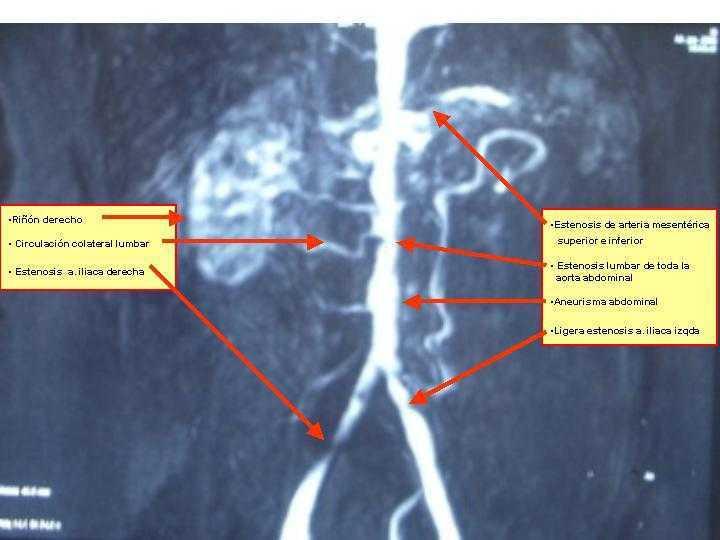

Debido a los hallazgos radiológicos de aneurisma y asimetría renal leve, solicitamos una angio-TC torácica en la que se evidencia un aneurisma de aorta descendente distal, de tipo sacular, de 4,3 cm de diámetro. Ampliamos estudio con una angio-IRM toráco-abdominal (figura 2, figura 3, figura 4, figura 5) en la que se observan signos de miocarditis. Estenosis en múltiples niveles de la aorta, con signos de inflamación activa y aneurisma focal de aorta torácica descendente. Afectación difusa de aorta abdominal, así como de sus principales ramas viscerales. Triple arteria renal derecha y doble arteria renal izquierda. Estenosis de la arteria polar superior izquierda.

Figura 5. Triple arteria renal derecha y doble arteria renal izquierda. Estenosis de la arteria polar superior izquierda.